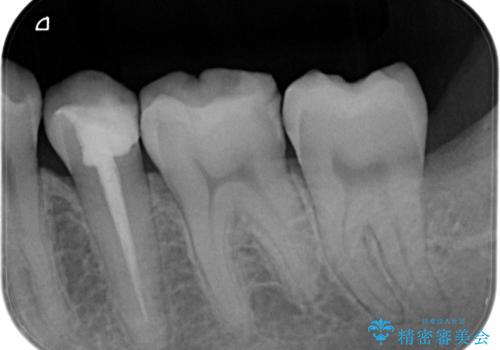

【オールセラミッククラウン】根管治療した歯の被せ物治療

- 根管治療した歯の被せ物の治療を希望され来院されました。

被せ物を行うことで、破折リスクを低下させることができます。

オールセラミッククラウン(スタンダード)で製作しています